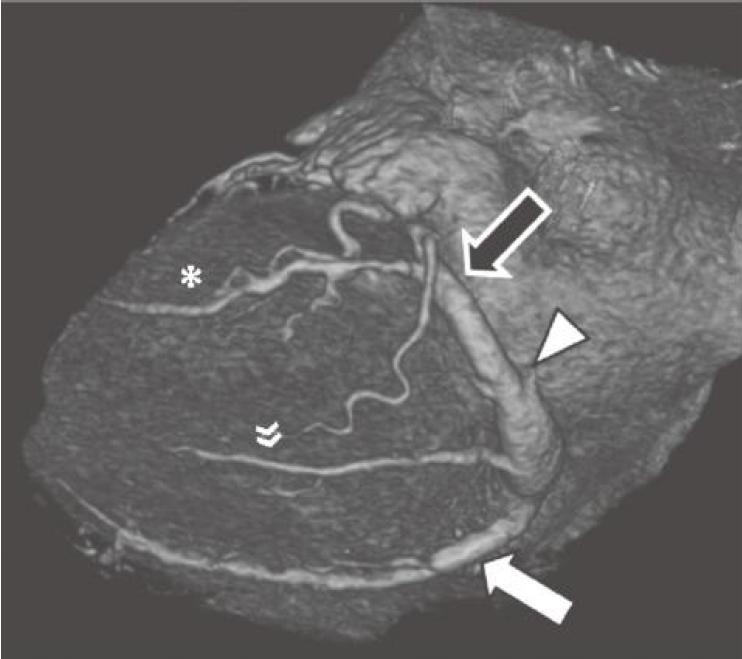

图13-4 RCA优势型,RCA绕过右心缘,在RAVG的下方发出后降支(箭),并走行于后室间沟(虚线)。心中静脉(箭头)也在后室间沟内走行

RCA.右冠状动脉;RV.右心室;LV.左心室